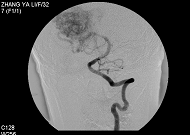

膽囊息肉內鏡圖(一)膽固醇息肉:此種類型的息肉最為多見,但它卻不是真正的息肉.而是膽汁中膽固醇的結晶集結在一起所形成的桑葚狀改變,其直徑大小多為1厘米以下。

3.內鏡超聲(endoscopicultrasonography,EUS)即經內鏡超聲掃描,是將超聲微小探頭安置在內鏡頂端,探頭為高頻,將內鏡插入消化道,進入十二指腸壺腹後此探頭更接近膽囊,可排除腸氣干擾或膽汁黏稠度等影響。EUS可將膽囊壁分為3層,內層為高回聲的黏膜及黏膜下層,中層為低回聲的肌纖維層,外層為高回聲的漿膜下層及漿膜層。如為息肉樣病變可見清晰的3層囊壁,而膽囊癌則囊壁的3層結構有不同程度的浸潤破壞。早期膽囊癌絕大多數是在結石和息肉等病變的掩蓋下發展的,早期缺乏特徵性聲像圖表現,鑑別困難。而EUS檢查觀察息肉樣病變與膽囊壁之關係,有助於鑑別診斷。朱燕陵等回顧分析了103例非結石性膽囊病變EUS檢查結果並與體表超聲及手術後病理進行比較,EUS檢查診斷正確率為75%,體表超聲為41.4%,EUS對膽囊息肉、膽囊癌、膽囊腺肌瘤診斷符合率為100%,體表超聲為55.6%。Sugiyama認為內鏡超聲(EUS)比BUS更準確,提供的圖像也更清晰。因194例PLG中,EUS判斷的136例非腫瘤性病變平均隨訪2.6年均未發現腫瘤;而BUS判斷的非腫瘤性病變中則有13%為腫瘤。EUS內層的回聲方式為細小聲點(tinyechonicspot)、聲點聚集(aggregationofechogenicspot)、微小囊腫(microcyst)及彗星尾征(comettailartifact)。如EUS證實既無細小聲點與聲點聚集,又無微小囊腫與彗星尾征時,應懷疑為腺瘤或癌腫。兩者無法鑑別,除非已浸潤至肝臟,但若為無蒂病變,則強烈提示為癌腫。結合組織學研究,一個細小聲點表示一群含有膽固醇泡沫的組織細胞,而無回聲區則為腺上皮增生。多個小囊腫和彗星尾征則分別為羅-阿竇增多和膽囊壁內結石所致。Gouma對31例PLG作CT與增強CT對比,CT僅發現14例(45%),而增強CT則為100%。因此,認為凡不增強CT已能發現的病變及增強CT發現的無蒂PLG均應診斷為腫瘤性息肉。有蒂與無蒂的診斷意義很大,20例有蒂PLG中6例為腫瘤(30%),而11例無蒂PLG中10例為腫瘤(91%)。增強CT診斷腫瘤性PLG的敏感性為88%,特異性87%,陽性預測率88%,陰性預測率87%,總準確率87%,結論為增強CT能鑑別腫瘤與非腫瘤性PLG,能可靠地篩選出應予切除的腫瘤性病變。